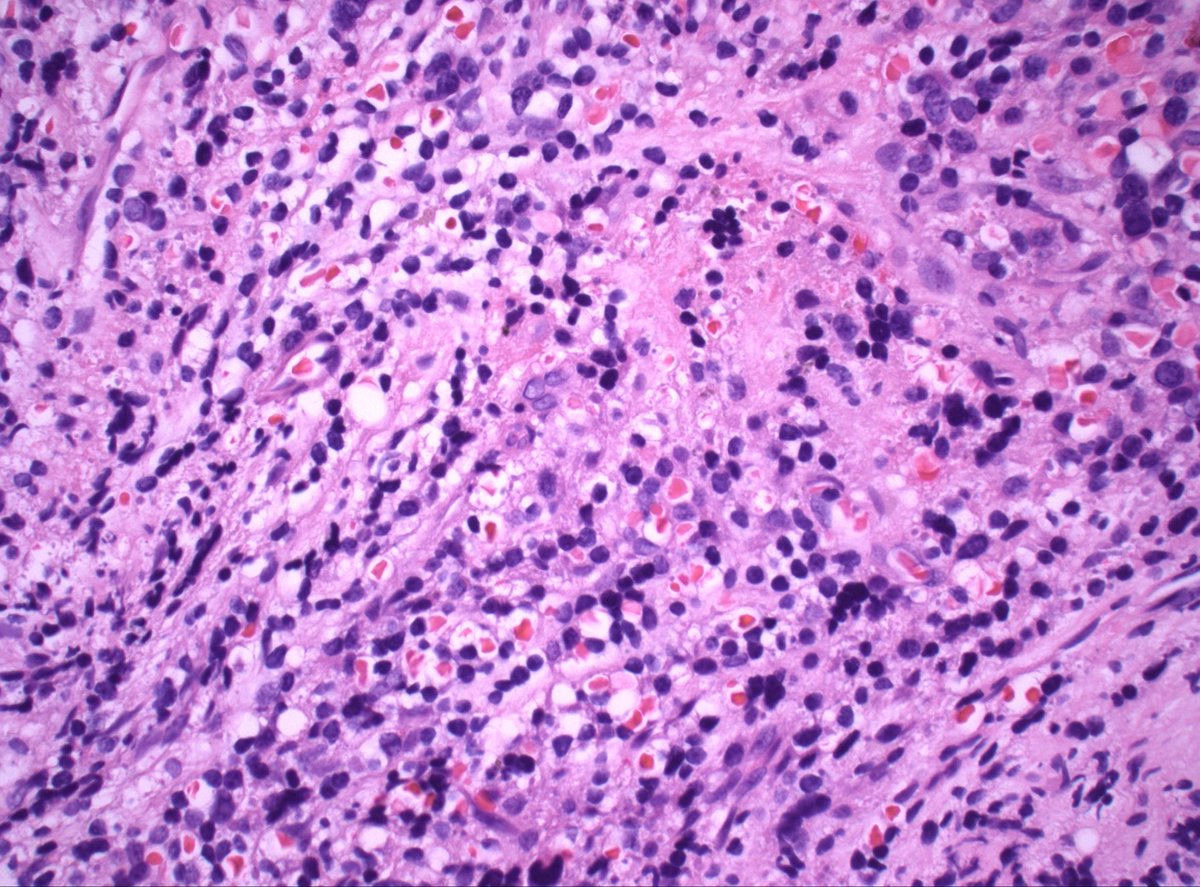

70s M h/o prostate cancer. Multiple bone lesions, this one from iliac. Dx/workup? #PathX #PathTwitter